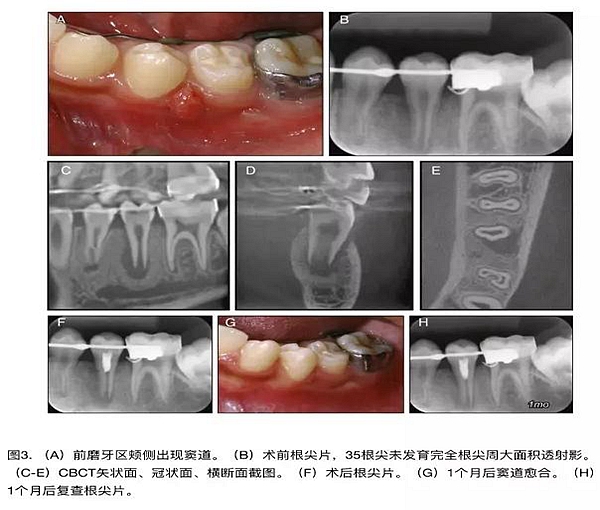

原則上年輕恒牙的牙髓治療應(yīng)盡可能以保存活髓的方式以便不影響牙根繼續(xù)發(fā)育。本文3個(gè)病例均描述了根尖尚未發(fā)育完成的下頜前磨牙被確診為牙髓壞死伴有大面積根尖病損,治療過(guò)程中在根管內(nèi)發(fā)現(xiàn)了部分活髓,而采用活髓切斷后都取得了很好的療效。